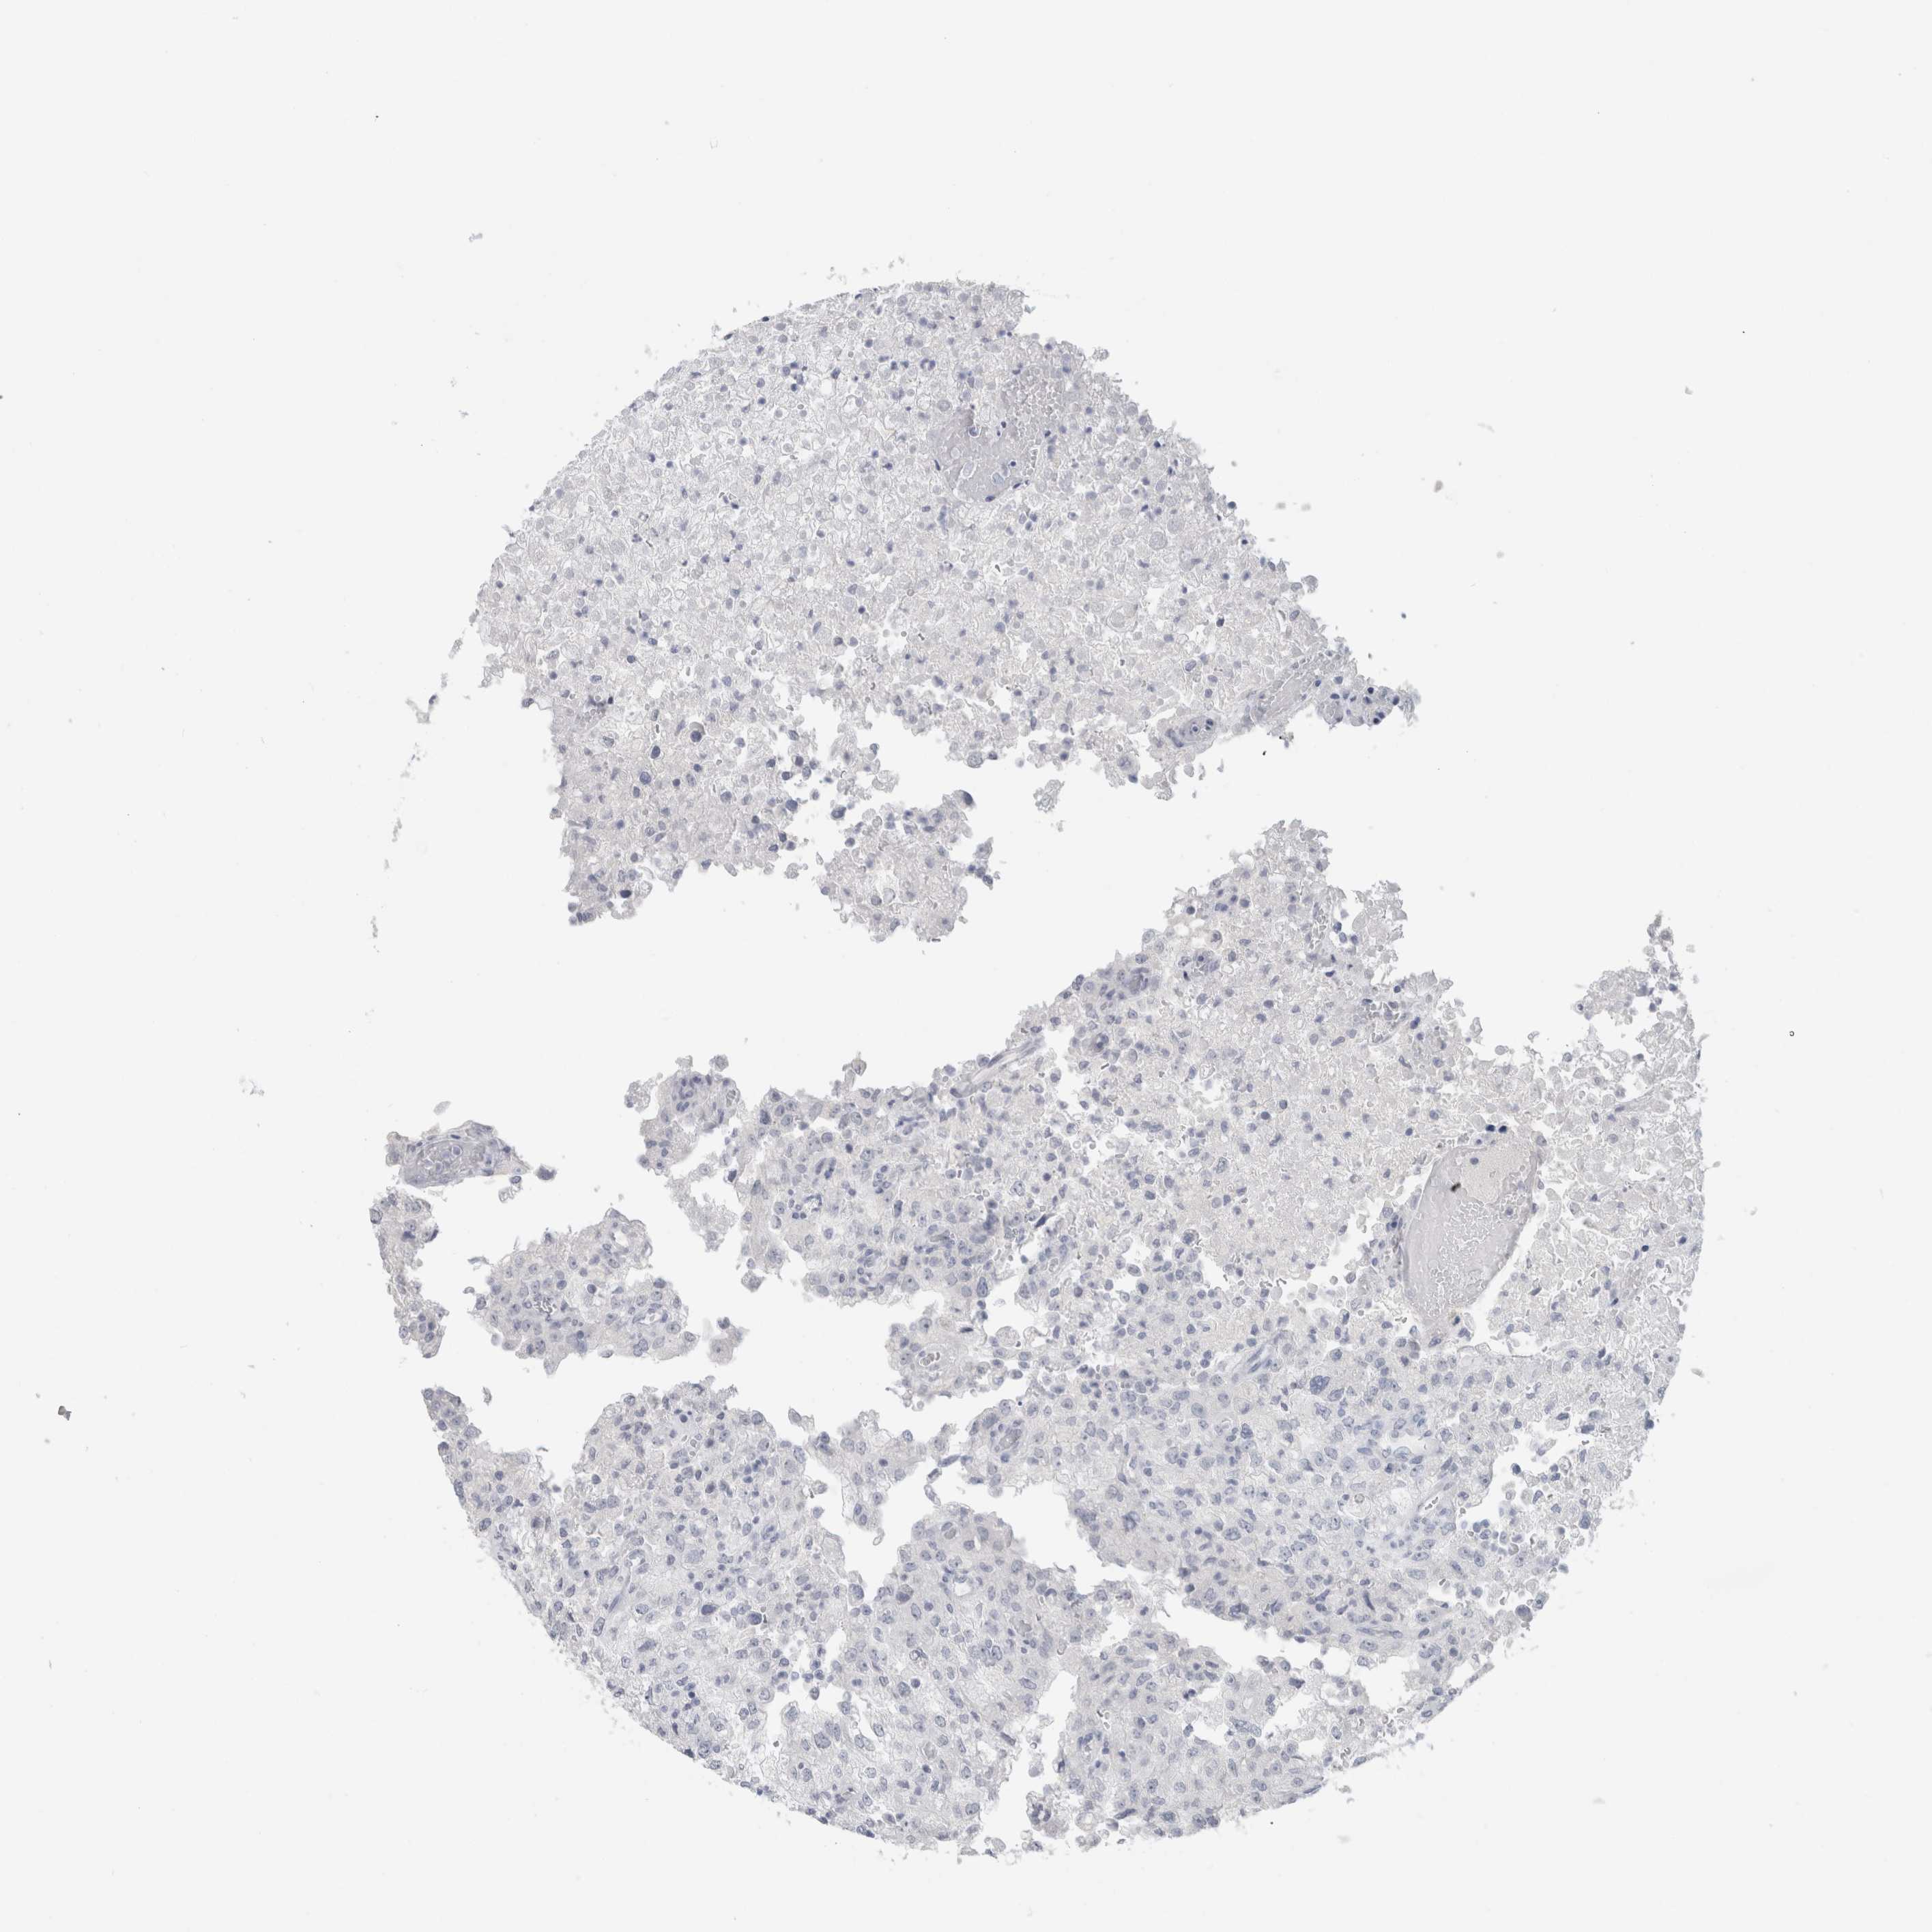

CANCER RENAL CANCER Show tissue menu

KICH TCGA KIRC TCGA KIRC VALIDATION KIRP TCGA PROTEIN RCC CPTAC PROTEIN EXPRESSION

BCAN is not prognostic in Kidney Renal Clear Cell Carcinoma (validation)